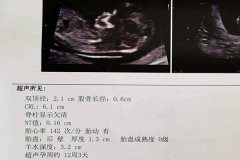

一般在怀孕50天左右做阴道B超是最适合,此时做阴道B超能详细知道孕囊状态以及胚胎发育情况。